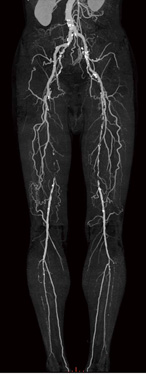

Add Vesselは,リージョングローイング法を使用しマウスの長押しのみで血管を自動追跡するため,描出したい血管を選択して描出するのが容易である。特に,CT Angioに求められる病変の支配血管の描出,完全閉塞等の症例における造影能が悪い場合の画像作成や,側副血行路の描出などは,Add Vessel機能により簡便に画像処理をすることが可能である(図3)。

図3 Add Vesselを用いて作成した臨床画像

右大動脈に75%の狭窄,左大腿動脈に90%の狭窄。

側副血行路にて,下肢血管を補っている。